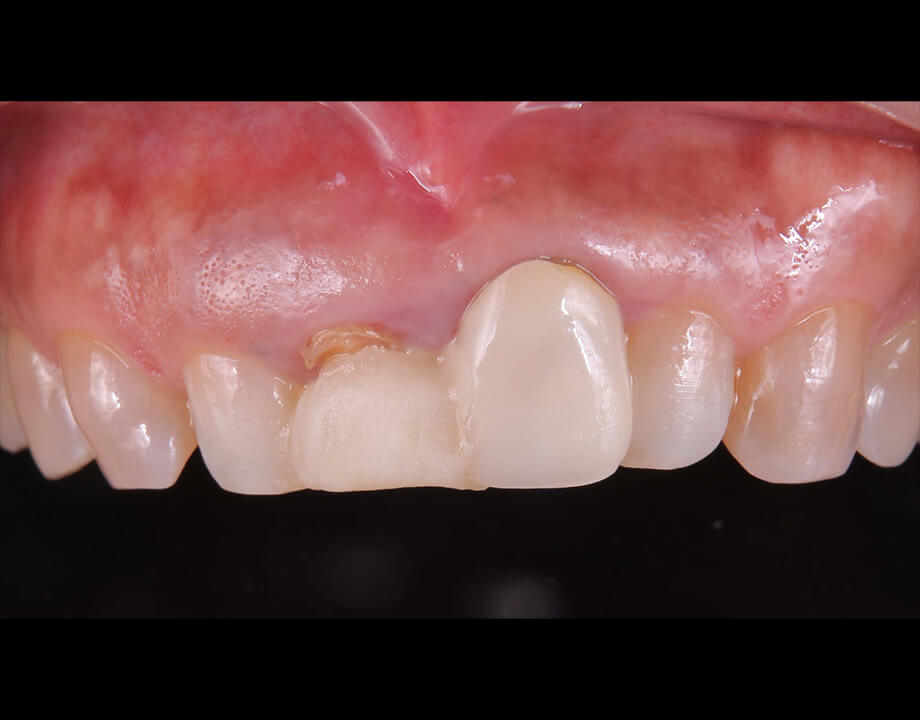

Case 01天然歯

ジルコニアレイアリング